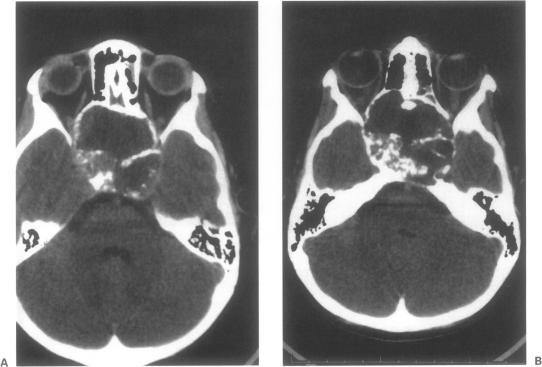

Although craniopharyngiomas account for a large percentage of pediatric intracranial tumors, there is a bimodal age distribution. Most of these neoplasms are suprasellar or sellar in location. In this report we describe an unusual case of an infrasellar craniopharyngioma in a child. Only four previous cases of infrasellar craniopharyngiomas with no sellar involvement have been described. Infrasellar craniopharyngiomas are part of the continuum representing intracranial craniopharyngiomas and ameloblastomas of the jaw. A transnasal endoscopic biopsy was performed with a preliminary diagnosis of craniopharyngioma. The patient then underwent a radical resection of the infrasellar tumor via a subfrontal transbasal approach. This case illustrates a rare and unusual location for a craniopharyngioma. Craniopharyngiomas should be considered in the differential diagnosis of infrasellar neoplasms. Infrasellar craniopharyngiomas compromise part of the spectrum of tumors originating from enamel-forming neural crest cells.

尽管颅咽管瘤在儿童颅内肿瘤中占很大比例,但存在双峰年龄分布。这些肿瘤大多位于鞍上或鞍区。在本报告中,我们描述了一例儿童鞍下颅咽管瘤的罕见病例。此前仅报道过4例无鞍区受累的鞍下颅咽管瘤病例。鞍下颅咽管瘤是颅内颅咽管瘤和颌骨成釉细胞瘤连续谱系的一部分。进行了经鼻内镜活检,初步诊断为颅咽管瘤。然后患者通过额下经基底入路对鞍下肿瘤进行了根治性切除。该病例说明了颅咽管瘤的一个罕见且不寻常的位置。在鞍下肿瘤的鉴别诊断中应考虑颅咽管瘤。鞍下颅咽管瘤是起源于形成釉质的神经嵴细胞的肿瘤谱系的一部分。